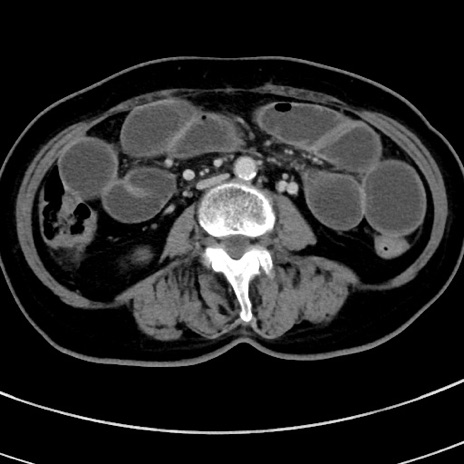

症例9(横断像)

【症例】 60歳代女性

【主訴】むかつき、みぞおちの痛み

【現病歴】3日前よりむかつきがあり、食事がとれない。

【既往歴】糖尿病

【身体所見】発熱なし、心窩部圧痛軽度あるも、腹膜刺激症状なし。

【データ】WBC 7400、CRP 1.92